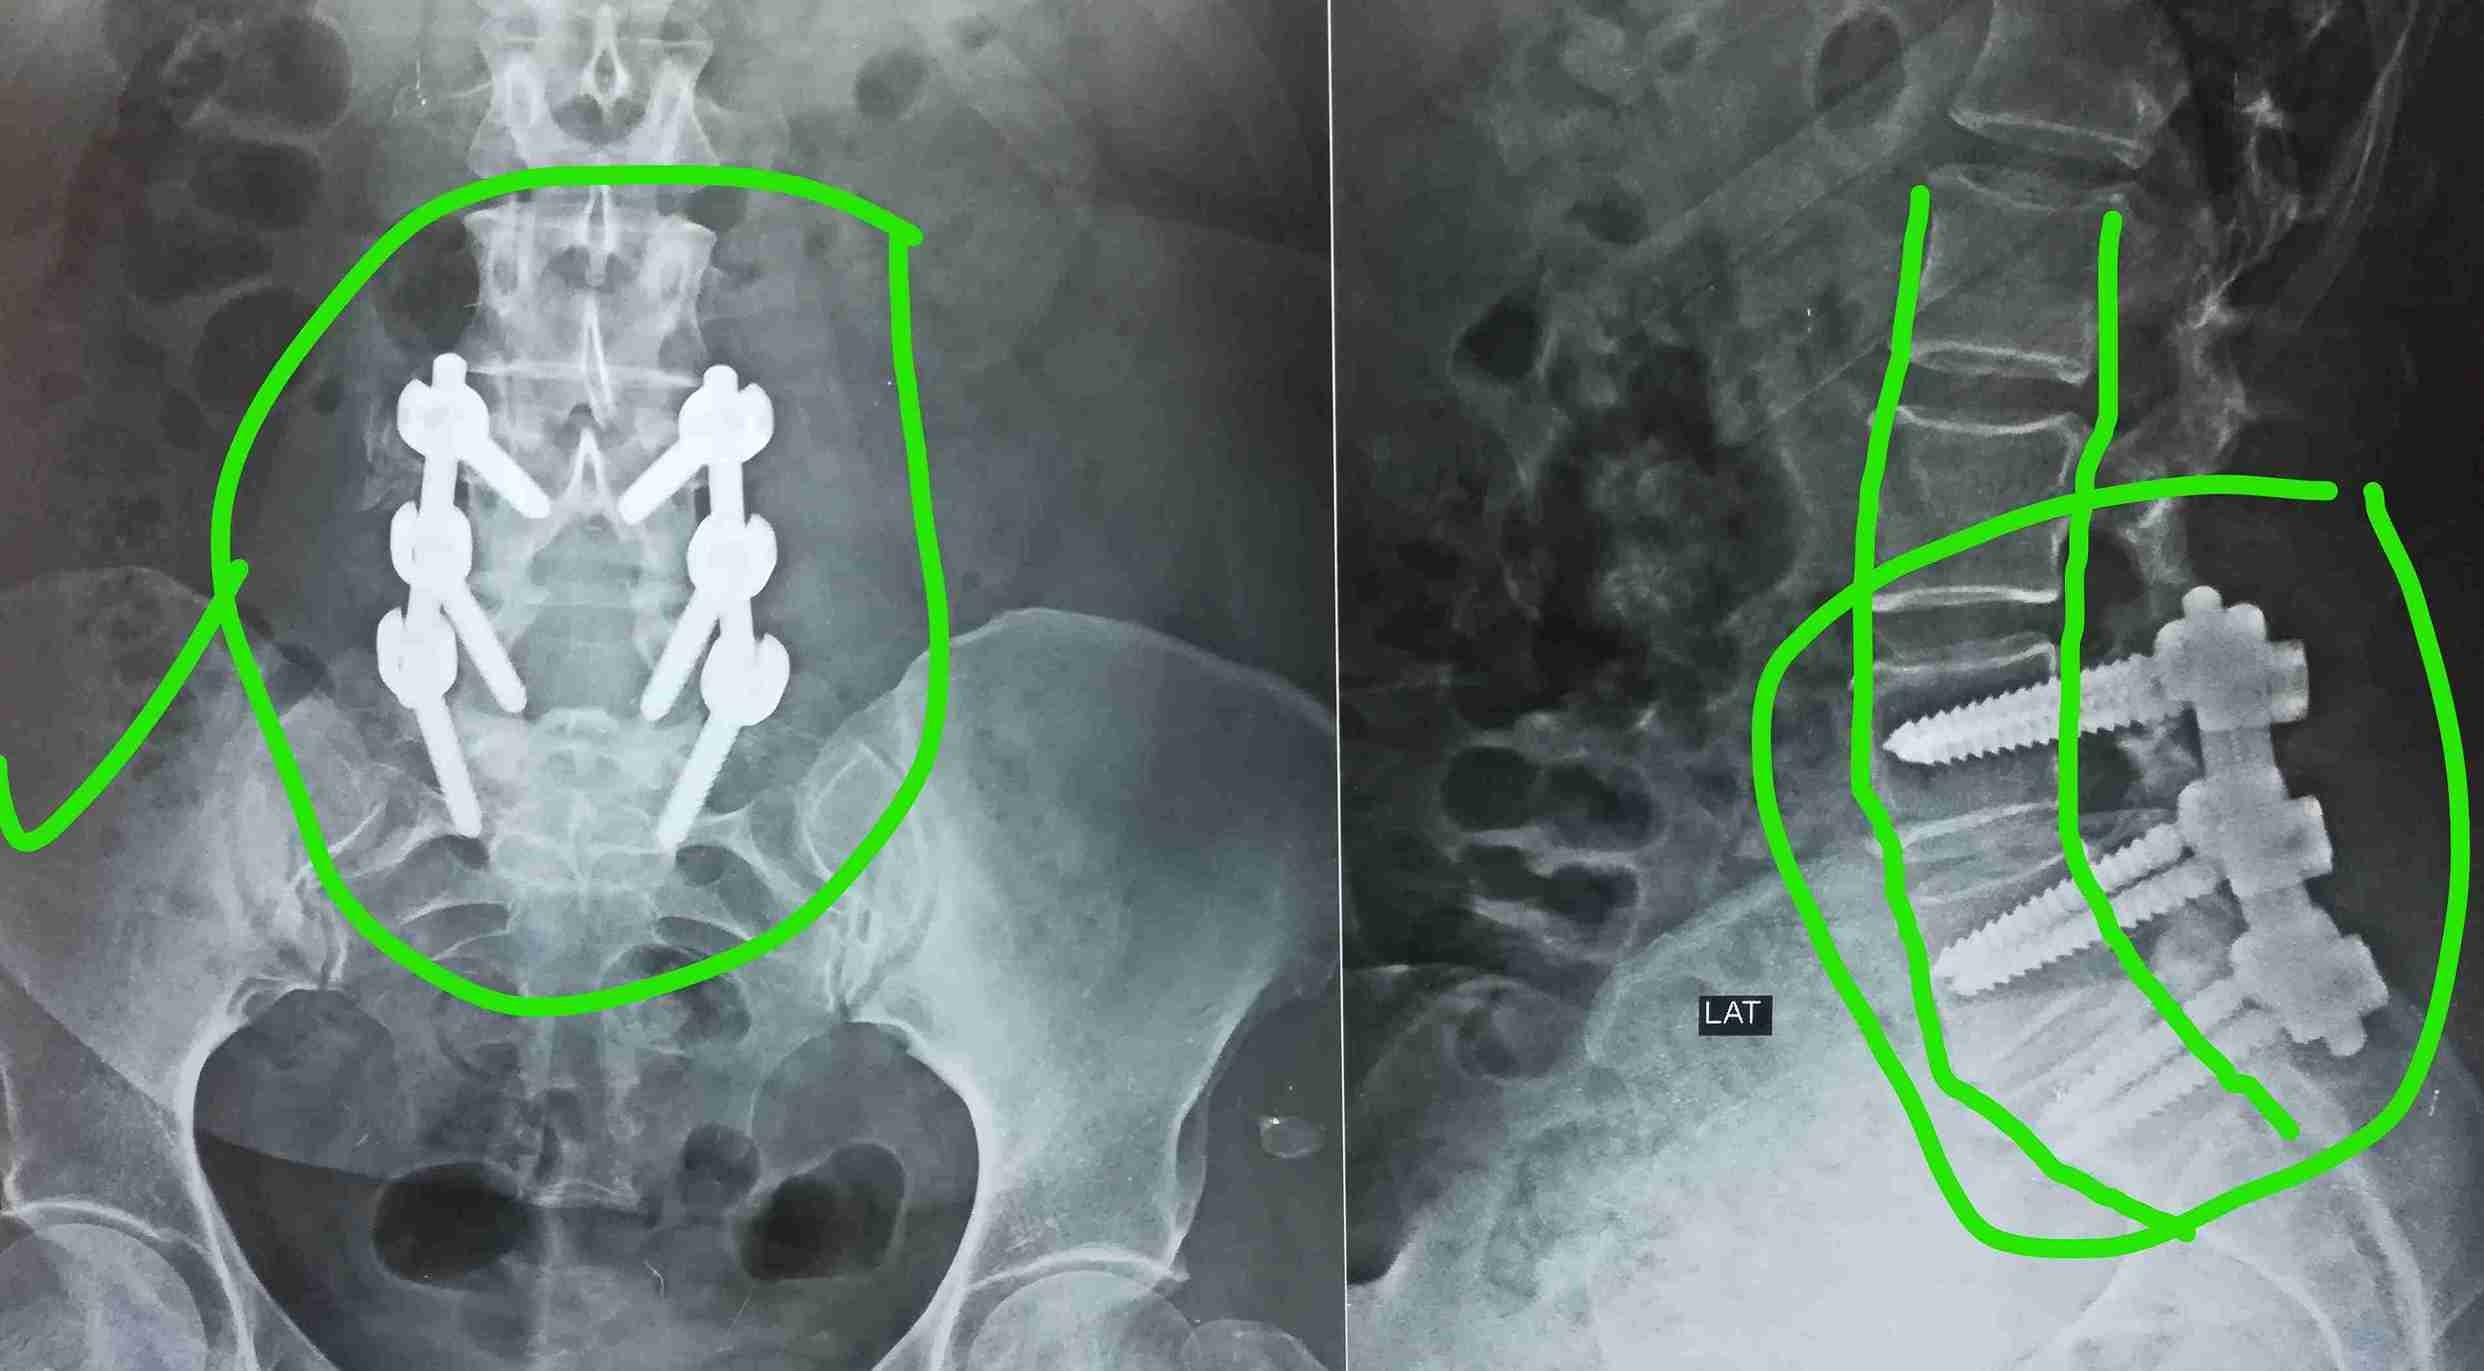

A successful surgery was performed to treat a herniated disc accompanied by spondylolisthesis. This condition causes severe back and leg pain due to pressure on spinal nerves, significantly affecting the patient's mobility and walking ability.

• Stabilizing slipped vertebrae in correct position

• Advanced internal spinal fixation